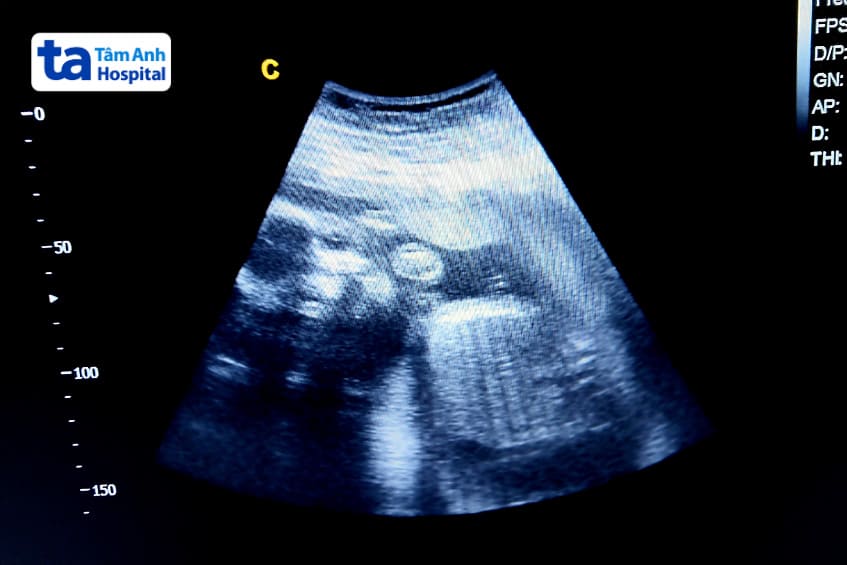

Đây là giai đoạn thai nhi phát triển nhanh chóng về cả kích thước và chức năng. Việc tầm soát, kiểm tra dị tật thai nhi trong giai đoạn này, đặc biệt qua siêu âm hình thái, là rất quan trọng. Các bác sĩ sẽ kiểm tra để phát hiện sớm những bất thường về cấu trúc và chức năng của thai nhi, đảm bảo thai kỳ diễn ra an toàn và bé phát triển khỏe mạnh.